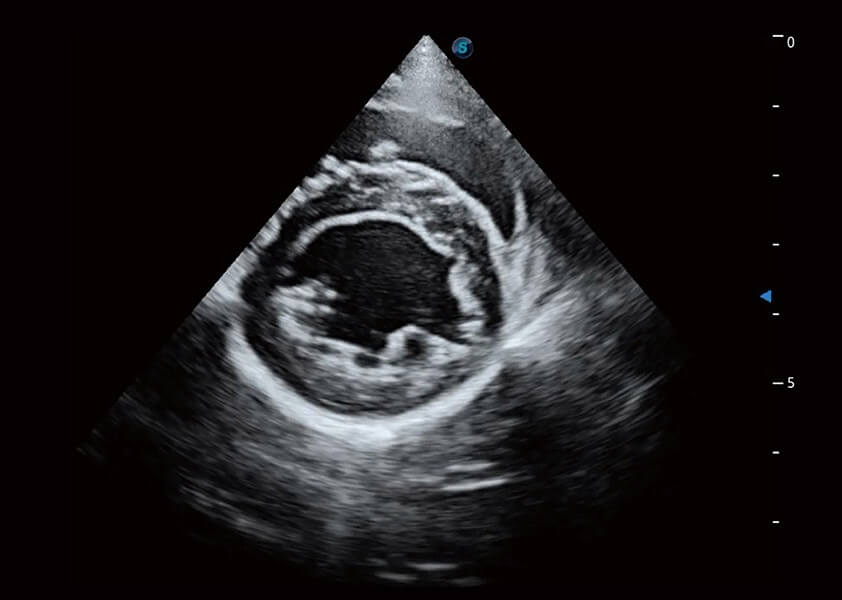

优异的基础图像

(猫)膀胱结晶